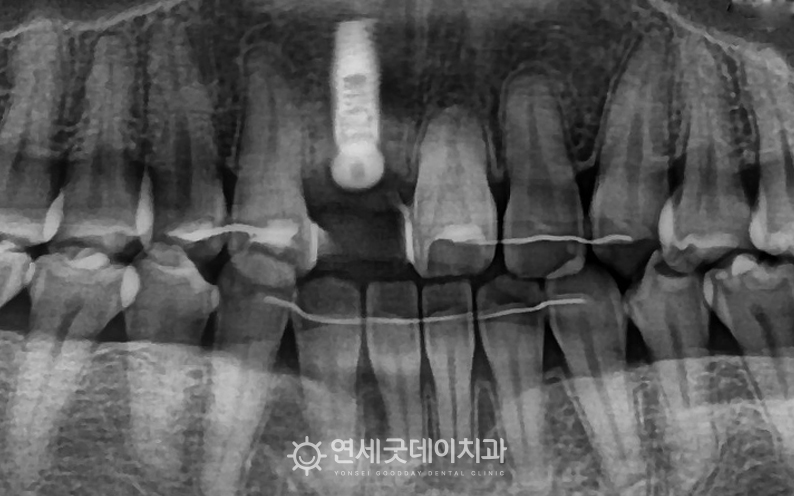

약 2개월 후 기존대비 잇몸뼈 높이와 두께가 보강되었으나 스트라우만은 70년 이상의 오랜 임상 데이터를 기반으로

검게 비어있던 잇몸 부위가 새로운 뼈로 채워지며